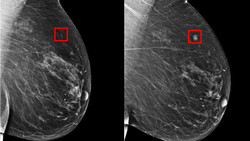

Өлкөдө көкүрөк рагы менен ооруган аялдар көбөйдү. Арасында илдетти өтүштүрүп, каза болгондору да бар